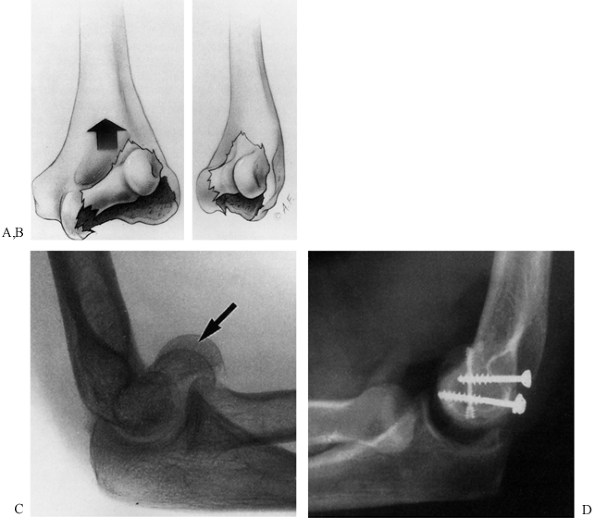

![]() |

Figure 16.3. Coronal shear fracture of the distal end of the humerus. A:

This vertical shear fracture involves the capitellum and most of the trochlea, resulting in separation, proximal migration, and rotation of the distal articular surface of the humerus. B: This anterior lateral oblique view shows that the main fracture line is in the coronal plane. C: Lateral radiograph showing the double-arc sign (arrow): One arc represents the lateral ridge of the trochlea and the other, subchondral bone of the capitellum. D: Postoperative lateral radiograph showing anatomic reduction of the fracture and internal fixation with two 4.0 mm AO screws and a Herbert screw. (With permission from McKee MD, Jupiter JB, Bamberger HB. Coronal Shear Fractures of the Distal End of the Humerus. J Bone Joint Surg [Am] 1996;78:49.) |